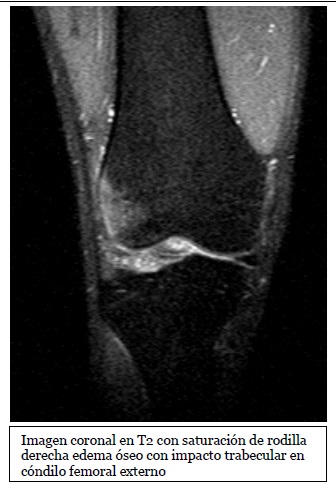

Imagen coronal de secuencia potenciada en T2 con saturación grasa de la rodilla derecha en paciente con lesión por traumatismo en valgo. Edema óseo en la

Fuente: https://epos.myesr.org/posterimage/esr/seram2014/124014/mediagallery/577012